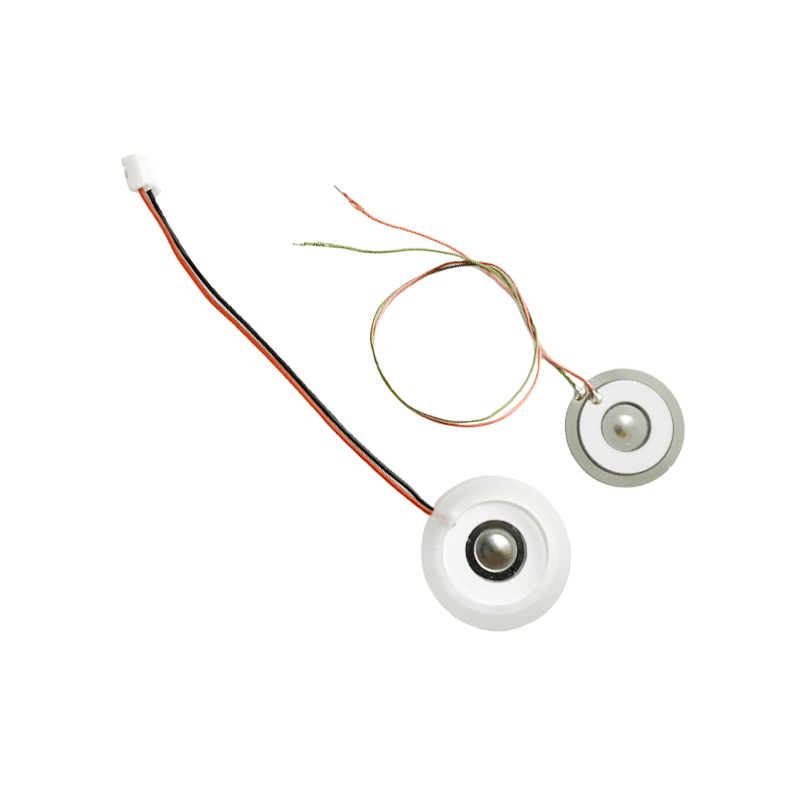

أقراص البخاخات الشبكية الطبية هي مكونات دقيقة تستخدم في الأجهزة الطبية لتحويل الأدوية أو المحاليل إلى جزيئات صغيرة من الهباء الجوي لعلاج اضطرابات الجهاز التنفسي المختلفة مثل الربو ومرض الانسداد الرئوي المزمن (COPD) وما إلى ذلك عن طريق الاستنشاق. يعد التصميم واختيار المواد لطبقة البخاخات أمرًا بالغ الأهمية لضمان توصيل الدواء بشكل فعال وراحة المريض. يتم ثقب ورقة الحجاب الحاجز غير القابل للصدأ بآلاف من الثقوب الشبكية الصغيرة مقاس 2-3 ميكرومتر في الصفائح الفولاذية من خلال تقنية الحفر بالليزر في عملية ليزر دقيقة، ومن ثم يتم ربطها بإحكام مع الصفائح المستديرة الخزفية الكهرضغطية، والتي تحول تردد الرنين للصفائح الكهرضغطية إلى طاقة اهتزاز عالية التردد من خلال إشارة الخرج للوحة تشغيل PCB، وتكسر بسرعة الدواء السائل إلى جزيئات الهباء الجوي الدقيقة. وتسمى هذه القطرات أيضًا بحجم الجسيمات المتوسطة، عندما تصل نسبة حجم الجسيمات المتوسطة D50 إلى> 60% أو أكثر، ستكون الجسيمات صغيرة بما يكفي لتتمكن من الوصول إلى عمق الرئتين إلى سطح الحويصلات الهوائية مع التنفس، وبالتالي تحسين كفاءة امتصاص الدواء والتأثير العلاجي. تحتوي صفائح البخاخات الشبكية الطبية الدقيقة بشكل أساسي على عدة أشكال، ورقة البخاخات الشبكية الدقيقة المصنوعة من الفولاذ المقاوم للصدأ، ورقة البخاخات الطبية بالنيكل والبلاديوم، ورقة البخاخات الطبية بوليمر PI، وما إلى ذلك. كل ما سبق يتم من خلال تحويل طاقة الاهتزاز الخزفي الكهرضغطي لتحقيق تأثير الانحلال.

رذاذ الموجات فوق الصوتية هو جهاز يستخدم مبدأ الاهتزاز بالموجات فوق الصوتية (تحويل الطاقة) لتحويل السائل إلى قطرات صغيرة. مبدأ العمل هو الخواص الكهرضغطية الفريدة للسيراميك الكهروإجهادي للقرار، قطعة الانحلال في استلام مطابقة إشارة المجال الكهربائي، ستنتج تردد التذبذب المقابل، من خلال دور الاهتزاز عالي التردد للتجويف السائل الذي يتم التخلص منه بعيدًا عن سطح الماء لإنتاج نوع من جزيئات ضباب الماء، متناثرة مع عدد كبير من الأيونات السالبة وجزيئات صغيرة من الجزيئات، يمكن تحقيق زيادة في الرطوبة المحيطة، ودور الهواء النقي. سطح الرذاذ مطلي بالمينا الزجاجية عند درجة حرارة عالية تصل إلى 800 درجة لحماية الأقطاب الفضية للصفيحة الكهرضغطية، وزيادة مقاومة الأحماض والقلويات ومقاومة الأكسدة للرذاذ، وزيادة عمر خدمة الرذاذ. يستخدم على نطاق واسع في أجهزة الترطيب الداخلية وأجهزة تنقية الهواء وعلاج البخاخات الطبية وسيارات التجميل وغيرها من المجالات، ولكنه مناسب أيضًا للمستودعات والمصانع والترطيب والتطهير لخلق جو من معدات الترطيب. تستخدم أقراص الضباب بشكل رئيسي في الترطيب الصناعي، والتعفير الطبي، والتعفير بالروائح العلاجية، والترطيب البيئي، وضباب الحديقة وغيرها من المشاهد.